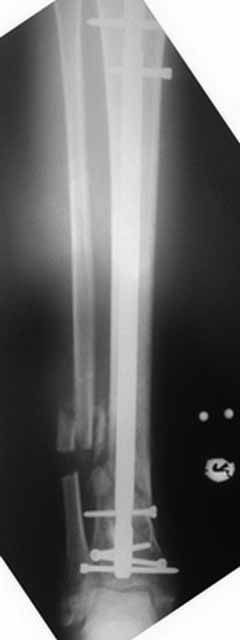

Примерная ситуация. Пациент 37 лет. Синтезировали где-то пластинкой. Попал к нам через 2 месяца.

19 апреля убрали через проколы пластину с винтами, пересекли fibula, наложили аппарат.

Немного потянули по оси, убрали вальгус, ротацию. 22 апреля (на 3-е сутки) заштифтовали окончательно. 29 апреля выписали из отделения. На все ушло 10 дней.